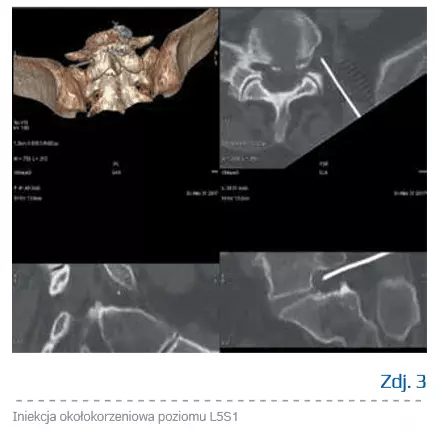

Technika iniekcji okołokorzeniowej pod kontrolą tomografii komputerowej z nawigacją

Pozycja pacjenta i przygotowanie toru igły przebiega tak jak w przypadku dyskolizy ozonowej, z tą różnicą, że teraz celem igły jest otwór międzykręgowy. Po zetknięciu igły z korzeniem pacjent zazwyczaj sygnalizuje ten fakt bardzo dobitnie, jednak w przypadkach nasilonych zmian wytwórczych pozycję igły trzeba potwierdzić w skanie kontrolnym i rekonstrukcji 3D. Następnie podaje się powoli mieszaninę leków, obserwując stan pacjenta, a po chwili mieszaninę gazu ozonowego w objętości 10–20 ml w zależności od tolerancji. Należy uprzedzić pacjenta o czasowym wyłączeniu funkcji ruchowej korzenia, a także o możliwości przejściowej zwyżki dolegliwości z powodu efektu objętościowego. Po obserwacji pacjent opuszcza klinikę zawsze w towarzystwie opiekuna. Kontrola wyznaczana jest z reguły po 2–3 tygodniach. W razie wyraźnej poprawy, w celu utrzymania efektu przeciwzapalnego możliwa jest kontynuacja leczenia kondycjonowaną surowicą autologiczną (autologic conditioned serum – ACS, terapia Orthokine).